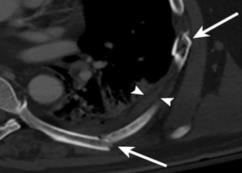

Rib fractures are a common and potentially severe injury that can be challenging and labor-intensive to detect in CT scans. While there have been efforts to address this field, the lack of large-scale annotated datasets and evaluation benchmarks has hindered the development and validation of deep learning algorithms. To address this issue, the RibFrac Challenge was introduced, providing a benchmark dataset of over 5,000 rib fractures from 660 CT scans, with voxel-level instance mask annotations and diagnosis labels for four clinical categories (buckle, nondisplaced, displaced, or segmental). The challenge includes two tracks: a detection (instance segmentation) track evaluated by an FROC-style metric and a classification track evaluated by an F1-style metric. During the MICCAI 2020 challenge period, 243 results were evaluated, and seven teams were invited to participate in the challenge summary. The analysis revealed that several top rib fracture detection solutions achieved performance comparable or even better than human experts. Nevertheless, the current rib fracture classification solutions are hardly clinically applicable, which can be an interesting area in the future. As an active benchmark and research resource, the data and online evaluation of the RibFrac Challenge are available at the challenge website. As an independent contribution, we have also extended our previous internal baseline by incorporating recent advancements in large-scale pretrained networks and point-based rib segmentation techniques. The resulting FracNet+ demonstrates competitive performance in rib fracture detection, which lays a foundation for further research and development in AI-assisted rib fracture detection and diagnosis.